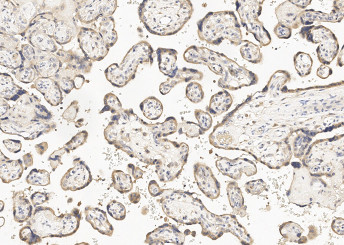

Product information "Anti-GDF15 Monoclonal Antibody"

| Application: | IHC (paraffin) |